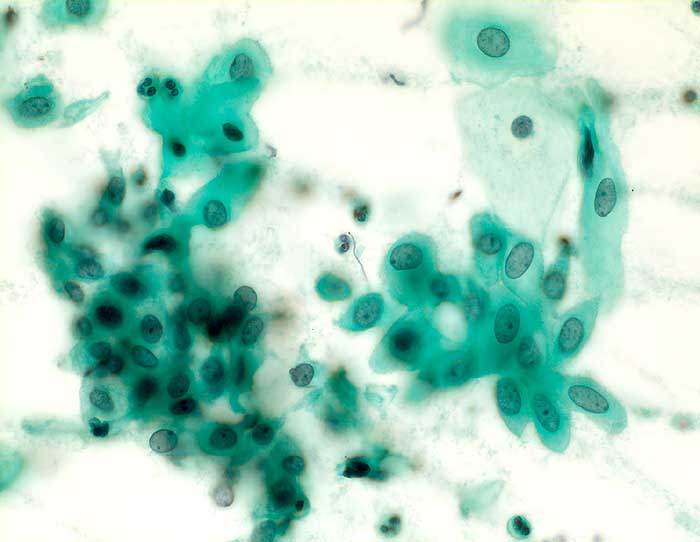

g/ Nicht klassifizierbare Plattenepithelien (ASCUS)

Nicht klassifizierbare Plattenepithelien (ASCUS)

Die Kategorie "atypical squamous cells of undetermined significance" der Bethesda Klassifikation umfasst entzündliche, reaktive und nicht klassifizierbare Plattenepithelveränderungen. Die Atypien übersteigen dabei das Mass gewöhnlicher reparativer Veränderungen. In den meisten Fällen sind reife Plattenepithelien betroffen. Nicht klassifizierbare Plattenepithelveränderungen können aber auch in metaplastischen oder atrophen Epithelien angetroffen werden. Die Diagnose ASCUS im atrophen Abstrich kann dann gestellt werden, wenn die Kerne mindestens zweimal so gross sind wie normal und eine deutliche Hyperchromasie zeigen, die Kernkontur bzw. Chromatinverteilung unregelmässig ist oder eine deutliche Pleomorphie in Form von Tadpole Zellen oder spindeligen Zellen vorhanden ist. In solchen Fällen kann nach einer kurzfristigen lokalen Östrogenbehandlung der Abstrich wiederholt werden. Gutartige atrophieassoziierte Veränderungen verschwinden unter Östrogentherapie. Signifikante präkanzeröse Läsionen persistieren hingegen und sind auf dem Hintergrund ausgereifter Zellen besser erkennbar.